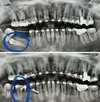

Ortodontik Malokluzyonlar

Diş Çapraşıklığı

Ortodonti